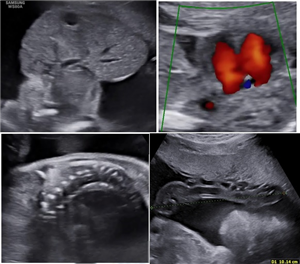

Báo cáo CLS: Một trường hợp chẻ mặt phức tạp